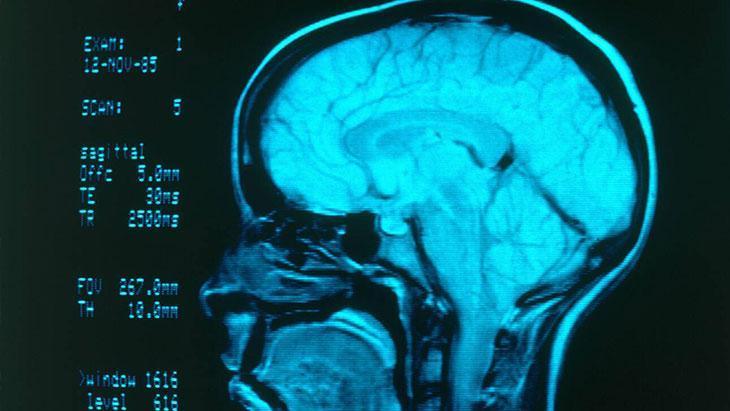

Sigaranın insan vücuduna verdiği zararlar saymakla bitmemesine rağmen "Günde 1 tane sigara içmek zararlı mı?" diye soran pek çok kişi var. Beyin ve Sinir Cerrahisi Uzmanı Op.Dr. Burak Kınalı, sigaranın özellikle beynin damar yapısını bozduğunu, tıkanıklıklara sebebiyet verdiğini ve beyin kanamasına davetiye çıkardığını söyledi. Peki şiddetli baş ağrısı beyin kanaması işareti mi? Beyin kanaması nasıl teşhis edilir? Beyin kanaması tedavisi nasıl olur? Sigaranın beyne verdiği zararlar nelerdir? Mutlaka okuyun...

Beyin kanaması riskine neden olan faktörleri açıklayan Beyin ve Sinir Cerrahisi Uzmanı Op.Dr. Burak Kınalı, sigaranın özellikle beynin damar yapısını bozduğunu, tıkanıklıklara sebebiyet verdiğini ve beyin kanamasına davetiye çıkardığını söyledi. Kınalı, başta yüksek tansiyon olmak üzere ileri yaş, obezite, kolesterol yüksekliği, aşırı alkol tüketimi ve damarsal bozuklukların da beyin kanaması riskini artırdığına değindi.

Beyin damarlarında büzüşmeye yol açıyor

Sigara, alkol ve uyuşturucunun direkt olarak beyin damarlarını etkileyen etmenler olduğunu dile getiren Op.Dr. Burak Kınalı, “Özellikle sigara, damar yapısını bozduğu, beyin damarlarında büzüşmeye, tıkanıklığa ve sertleşmeye sebep olabildiği için beyin kanama riskini ciddi oranda artırabilir.

Beyin damarlarının elastik yapısının bozulması ve yüksek tansiyon gibi faktörler de eklenirse beyinde baloncuk (anevrizma) riskini artırarak yüksek oranda ölümcül seyredebilecek olan beyin kanamasına yol açabiliyor.

Op.Dr. Kınalı, beyin kanamasının nasıl tedavi edildiğiyle ilgili şunları söyledi: "Başvuru yapan hastanın detaylı ve hızlı muayenesinden sonra hekimin kararına göre beyin kanaması düşünülen hastalarda acil şartlarda çekilecek olan beyin tomografisinin en hızlı tanı yöntemi olduğu, buna ek olarak gerek duyulması halinde etkenin belirlenmesi için MR veya anjio yapılmasının uygun olacağını belirtti. Beyin kanamasında tanıda altın standart ise kasıktan anjiyo işleminin uygulanmasıdır."